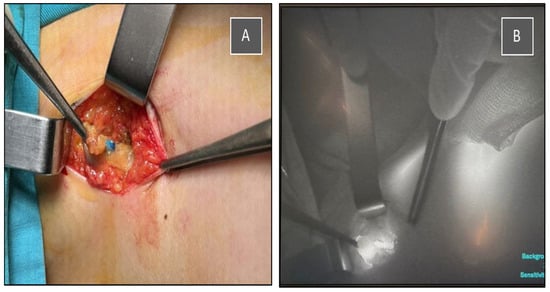

The multidisciplinary team decided to perform, in the same procedure, a partial resection of the right breast with tumor localization and sentinel lymph node biopsy using dual tracers (indocyanine green—ICG and methylene blue), as well as left nephrectomy, which was successfully carried out in our institution (Figure 3, Figure 4 and Figure 5).

Figure 3. Intraoperative identification of the sentinel lymph node using a dual tracer method. (A) Blue-stained lymph node visualized after methylene blue injection. (B) Indocyanine green (ICG) fluorescence imaging of the same sentinel node using a near-infrared camera system.